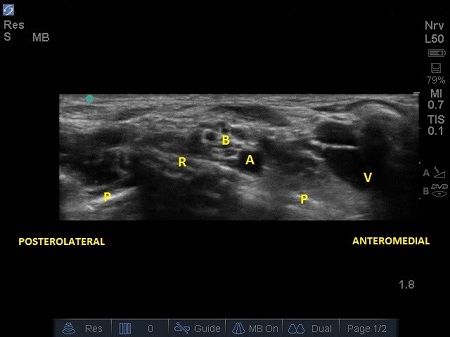

- The subclavian vein (V) is found more medially to the artery. The anterior scalene muscle inserts onto the first rib between these two vessels (A and V), but occasionally there are anatomical variations (4) where both vessels are together between the insertions of both the scalene muscles (anterior and middle ones).

- A linear hyperechoic structure immediately deep and lateral to the A is the first rib with its bony shadow. However, in small children the cortical layer of ribs is thin enough that you can see both layers of the rib cortex and visualise lower down another bright line: the parietal and visceral pleura interface. See Fig. 3.

Fig. 3. Sonoanatomy of infant supraclavicular region. A – Subclavian artery. B – brachial plexus, P – pleura, R – first rib, V – subclavian vein